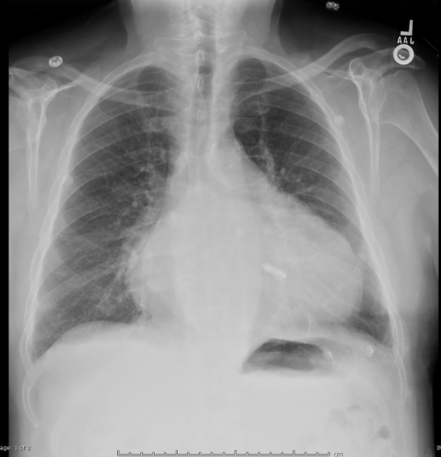

Complication after Nissen fundoplication with this postop barium swallow and EGD view looking at the hiatus

What is a slipped wrap?